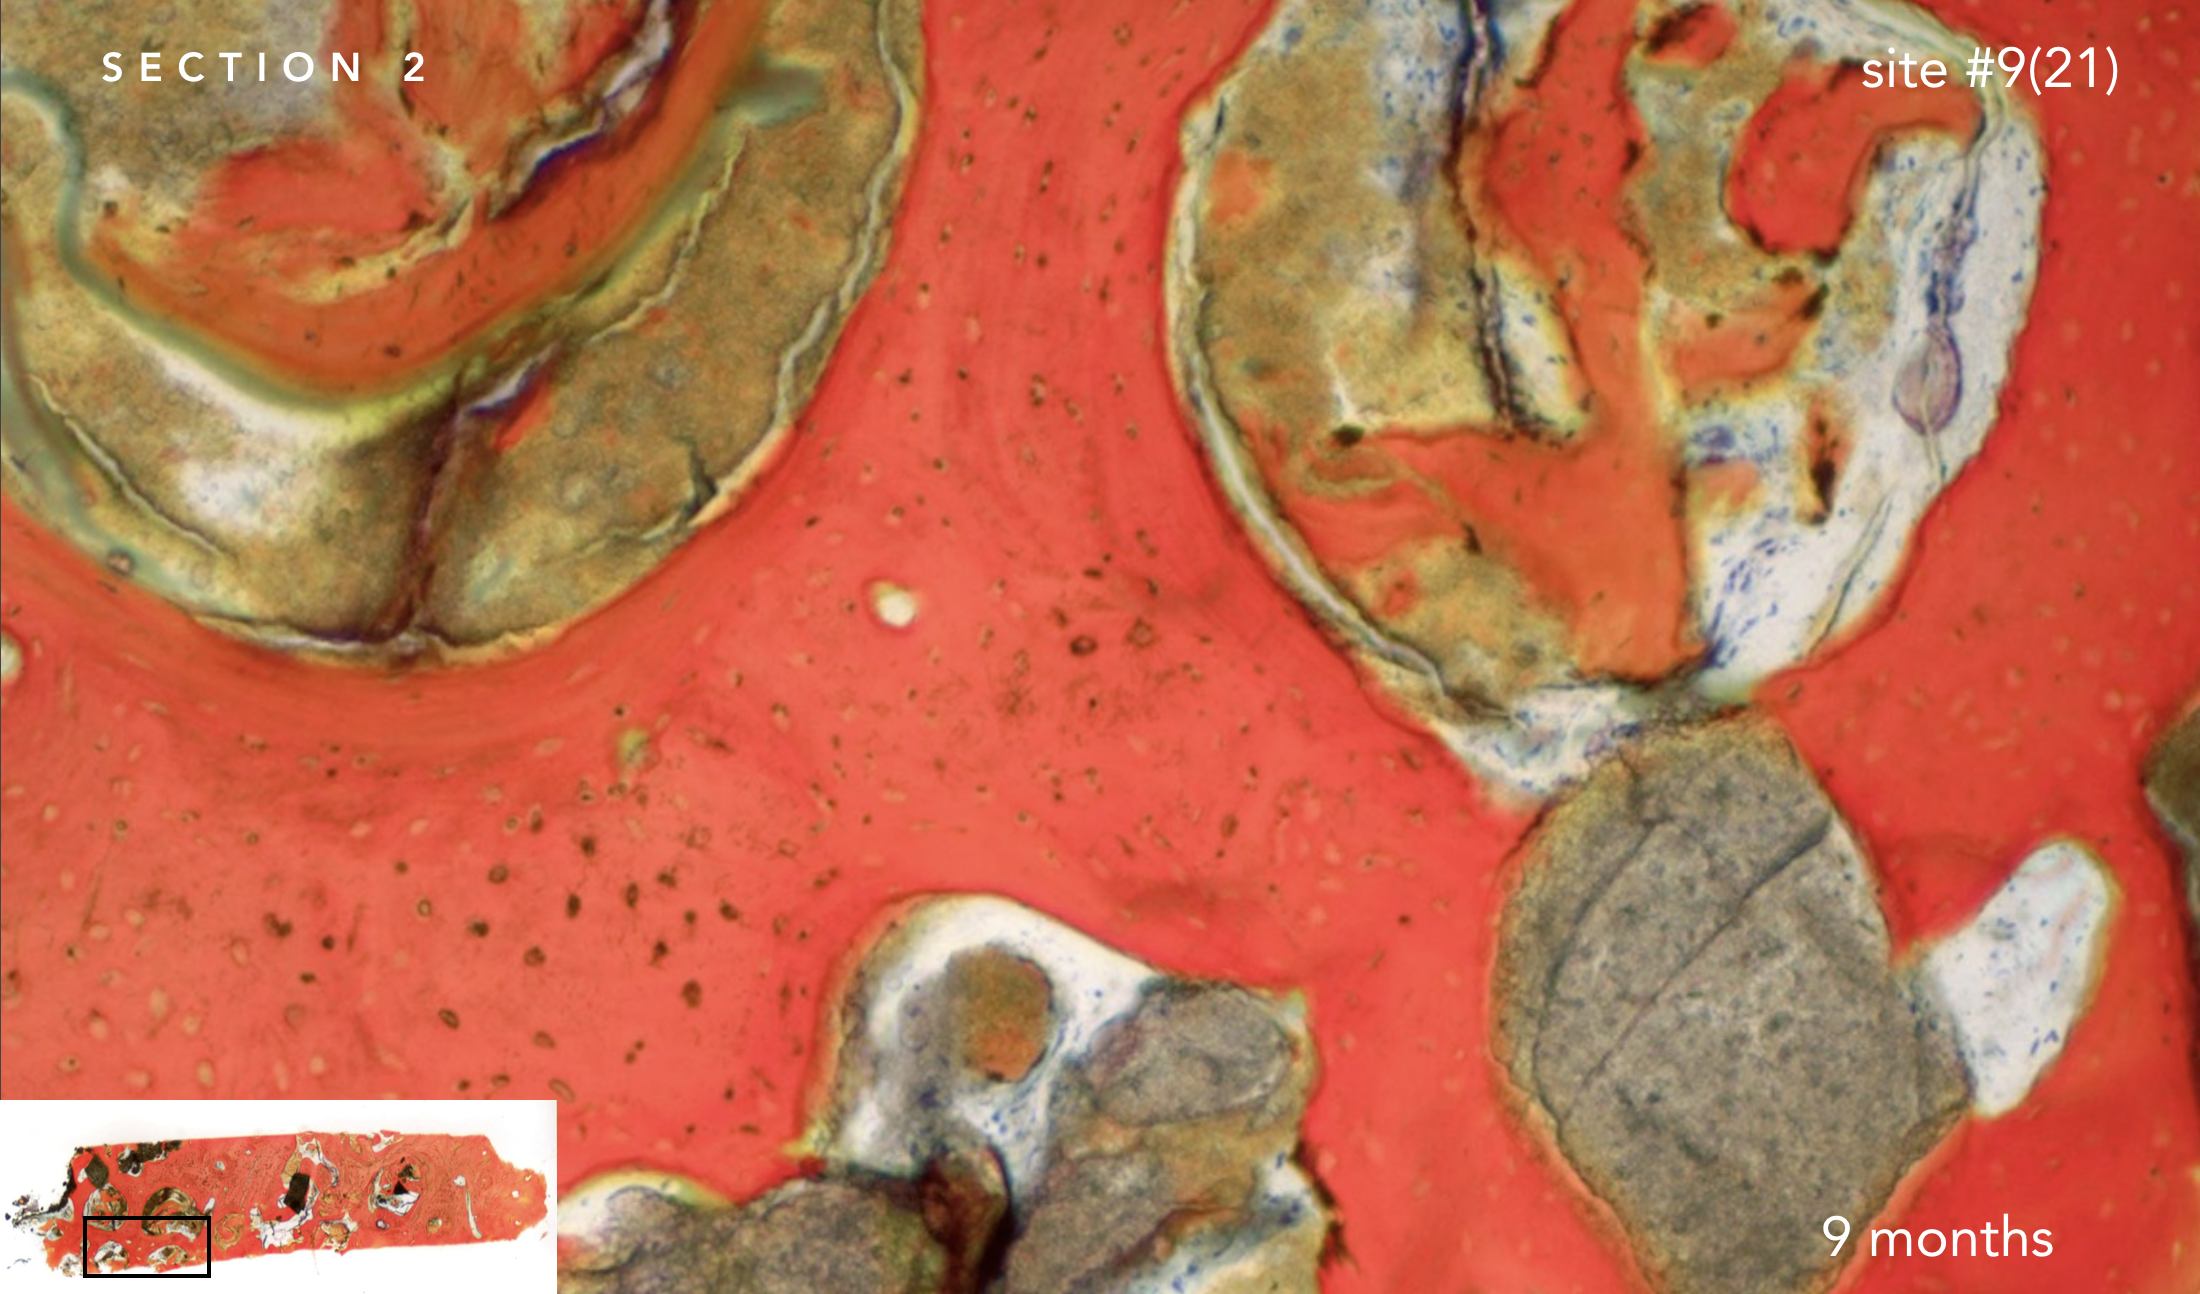

With the patient’s consent, a core specimen was harvested during the osteotomy preparation for implant #9(21) and sent for histologic analysis.

The interstitial and concentric lamellar bone patterns observed are consistent with the appearance of healthy, orderly, living bone.

With the patient's authorization, a specimen was harvested during the osteotomy preparation for implant on site #9(21) and sent for histologic analysis.